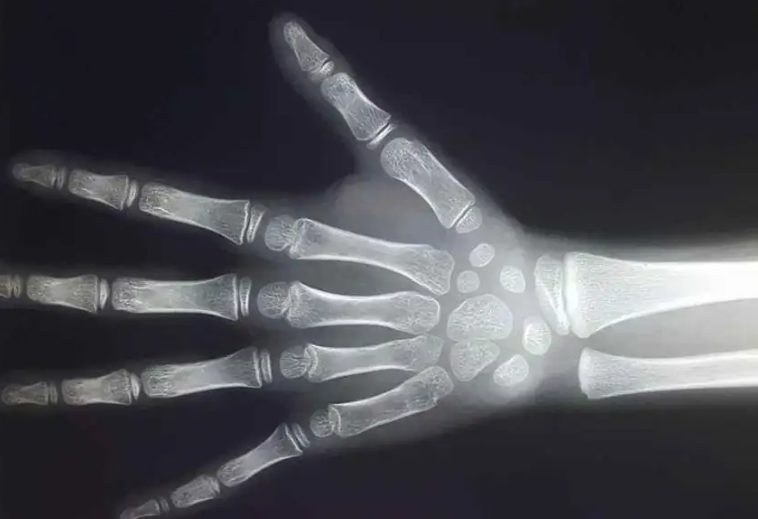

您的孩子查骨龄了吗

相信所有父母在带小孩去医院查看生长发育状况的同时,一定也为小儿拍摄了骨骼的成长年龄片了。骨龄究竟是什么呢?它为何这样重要?

人类骨头成长的变化基本相同,每一种骨骼的成长进程都存在持续性和年龄阶段性。各个年龄阶段的骨骼存在不同的外形特征,所以,骨龄评估可以比较精确地反应个体的成长水平和完善程度。它不但有助于判断孩子的生物学年龄,同时还有助于通过骨骼的发育年龄及早知道孩子的成长潜力及其性成熟的趋向。通过骨骼的成长年龄还可以预知孩子的成年身高,骨骼年龄的检测还对某些儿科门诊内分泌病变的治疗有重要帮助。同时对某些体格矮小的患儿的诊断有重要的指导意义。